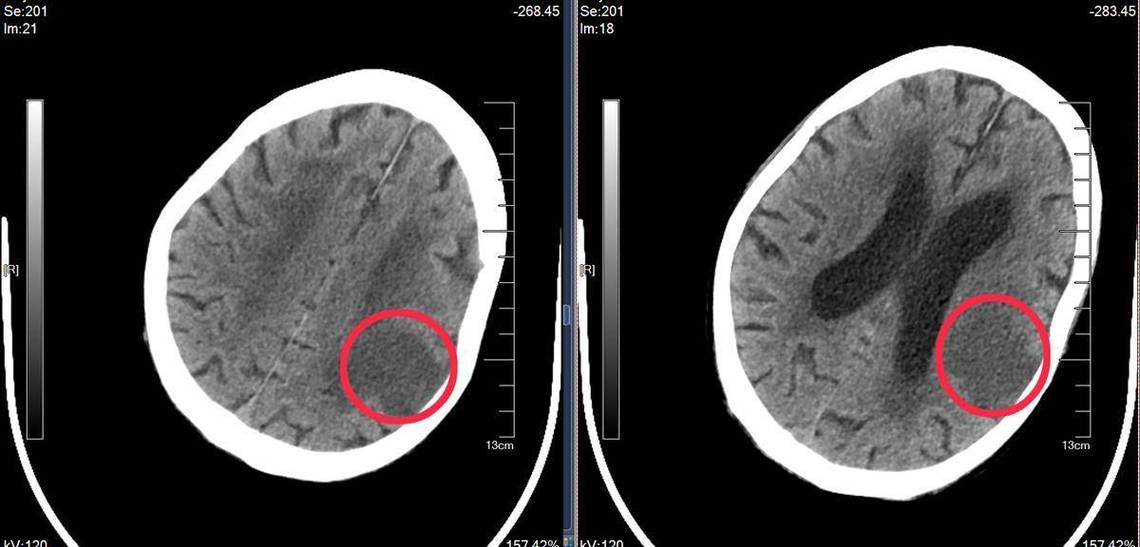

- 通常在发病6-24小时后,坏死的脑组织会因为水肿(肿胀)和细胞结构被破坏,在CT图像上呈现出低密度的阴影(也就是看起来更“黑”的区域)。

- 医生会根据这个低密度影的位置、形状和范围来判断是哪个血管供血的区域出了问题,从而推断出梗死的部位和大小。

CT的主要作用是“排除”:

- 在急诊,CT的首要任务之一是排除其他可能引起类似症状的疾病,特别是脑出血。

- 脑梗死的CT图像上表现为“白色区域变黑”,而脑出血则表现为“黑色区域变白”(高密度影),这两种病的治疗原则完全相反,所以必须第一时间用CT来区分。